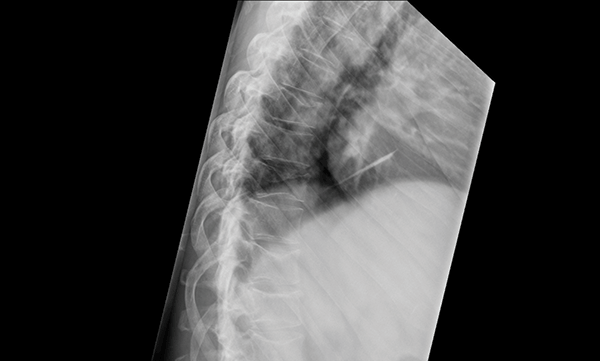

Other symptoms of advanced multiple myeloma include unusual fractures shortness of breath weakness feeling very thirsty and belly pain. If myeloma weakens the bones in the spine they can collapse and press on spinal nerves. Multiple myeloma can also cause nerve damage or pain when a tumor presses up against a nerve.

But when you have late-stage multiple myeloma your symptoms may show up as. Multiple myeloma end stage what to expect. Tumors can also compress the spinal cord which can result in back pain and.

This is called spinal cord compression and can cause. Stage 3 shows that there is a greater number of myeloma cells in the body. Most patients 866 were alive and still attending the Multiple Myeloma Palliative Care Clinic at study end.

1 pain from myeloma bone disease MBD. The best people to ask would be someone in their medical. Ad FDA Approved CAR T RR MM Treatment Option For Patients.

Cancerous plasma cells can interfere with bone formation and maintenance.